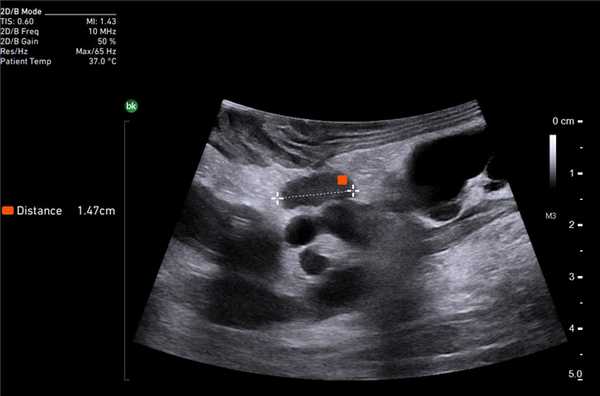

У 5 (41,7%) из 12 пациенток образования в печени имели гиперэхогенную, гомогенную структуру с четкими и ровными контурами размером от 5 до 12 мм в диаметре, которые были интерпретированы как доброкачественные образования печени — гемангиомы (табл. 2). У 4 (33,3%) пациенток образования имели анэхогенную гомогенную структуру, с четкими и ровными контурами, с гладкой внутренней выстилкой и эффектом усиления эхосигнала, размером от 3 до 11 мм в диаметре, и были интерпретированы как кисты. В 3 (25%) случаях в печени были выявлены гипоэхогенные образования солидной гетерогенной структуры с нечеткими, но ровными контурами размером от 10 мм в диаметре (рис. 1) до 22×17×15 мм в одном случае, расположенное на диафрагмальной поверхности печени, которое «самоампутировалось» в процессе исследования и при срочном гистологическом исследовании оказалось метастазом аденогенного рака (рис. 2).

Рис. 1. Эхограмма. Интраоперационное УЗИ печени (стрелкой указан метастаз рака яичника).

Клинический пример N2. Пациентка Р. находилась на лечении в ГУРОНЦ РАМН. При прохождении обследования был установлен диагноз рак толстой кишки. По данным ультразвуковой компьютерной томографии на фоне выраженной диффузной неоднородности паренхимы печени очаговые образования не определялись. При проведении ангиографии и компьютерной томографии так же убедительных данных за наличие метастазов в печень получено не было. При интраоперационном ультразвуковом исследовании были выявлены два очага, характерными особенностями которых являлись малые размеры (0,2 - 0,4 см), а так же нечеткость контуров и изоэхогенность структуры (рис. 1 а,б).

Рис. 1. Метастатические очаги (стрелки) в печени при интраоперационной ультразвуковой томографии.